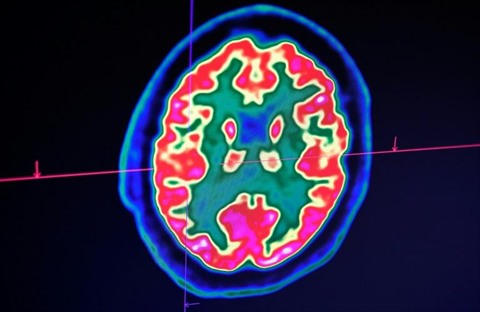

| Des médecins ont constaté chez des malades graves du COVID-19 des symptômes neurologiques allant de la perte d'odorat à des douleurs nerveuses, et jusqu'à des crises convulsives et des accidents vasculaires cérébraux |

Des études commencent à décrire le phénomène. Dans la revue de l'Association de médecine américaine (JAMA), la semaine dernière, des médecins ont rapporté que 36% de 214 patients chinois avaient des symptômes neurologiques, allant de la perte d'odorat à des douleurs nerveuses, et jusqu'à des crises convulsives et des accidents vasculaire cérébraux (AVC).

Dans le New England Journal of Medicine, la revue médicale américaine la plus cotée, des médecins français à Strasbourg ont décrit que plus de la moitié de 58 patients en réanimation étaient confus ou agités. Des scanners des cerveaux ont révélé de possibles inflammations. "Tout le monde dit que c'est un problème de respiration, mais cela affecte aussi quelque chose qui nous est très précieux, le cerveau", dit S. Andrew Josephson, chef du département de neurologie à l'université de Californie San Francisco.